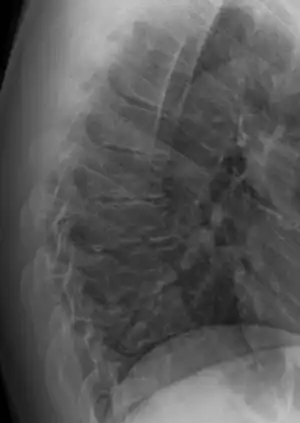

Diagnosis is typically by medical imaging. The degree of kyphosis can be measured by Cobb's angle and sagittal balance.